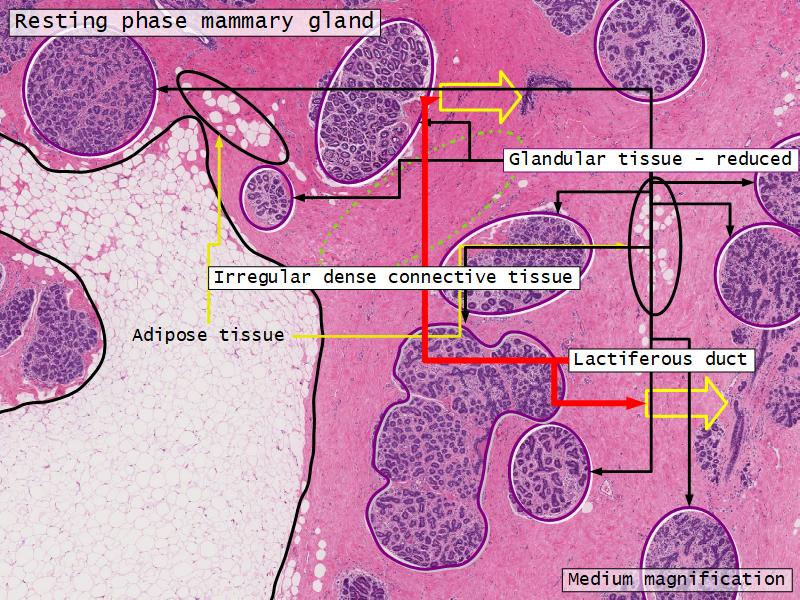

Mammary gland

Write short notes describing the structure of the mammary gland.

(5)

Mammary gland

- Compound tubuloalveolar gland

- 12 - 20 glands

- Each with own lactiferous duct

- Each with own lactiferous sinus

- Opens on skin at apex of nipple

Two stages

- Resting

- Active

Resting and active

Describe the resting mammary gland and compare with the active gland.

(8)

Resting gland

- Connective tissue dominate

- More adipose tissue

- Glandular tissue reduced

Active gland

- Terminal ducts expand

- Forms alveoli

- Connective tissue reduced

- Adipose tissue reduced

- Glandular tissue dominate

Structures

List the structures and cells found in the mammary gland.

Structures

- Lactiferous sinuses

- Stratified squamous near opening on skin

- Stratified cuboidal other parts

- Lactiferous ducts

- Stratified cuboidal

- Myoepithelial cells

- Underlie lactiferous ducts in most areas

- Basal lamina

- Separate epithelial components from stroma